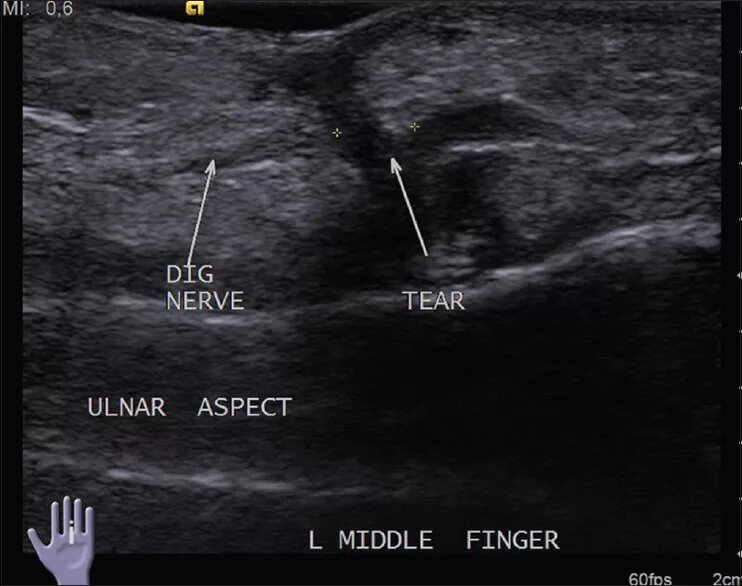

Узи нервов сделать в москве